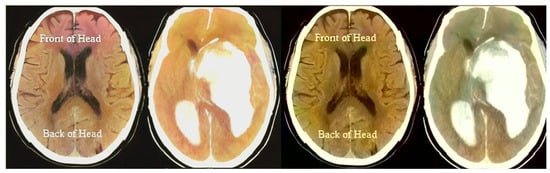

The “dwt2” method is used for the conversion. In the DWT process, the original image is decomposed into up to two levels using the “Haar” wavelet. This decomposition produces horizontal, vertical, diagonal, and proximity components. The decomposed components are reconstructed using the DIWT to recover the original image. This strategy is illustrated in Figure 2, and the compression method takes a decomposed image as input and compresses it using a wavelet packet compression technique using “Haar” wavelet packets. The compression method, “wpdencmp,” uses a soft thresholding technique that uses wavelet packets to compress the image and compute the threshold. This compression concept is illustrated in Figure 3, along with histograms of the original and compressed images. A step-by-step compaction process is shown in Figure 4. At each level, the images are refined, and the differences between levels are visible. The higher the number of coding levels of compression, the higher the image’s compression ratio and recovered energy. The compressed image is decompressed by wavelet packet reconstruction using the accounting matrix values of the decomposed image. Horizontal, vertical, diagonal, and proximity components are extracted from the decompressed image, and an IDWT is applied to recover the original image. A title image embedded in the patient data is visualized.

Figure 4.

Applying DWT.

In Figure 3, the steganography image of the brain hemorrhage is taken, and DWT is applied. After compression, the compressed image is displayed as a bar graph. The wavelet reconstruction method recovers the compressed image from the compressed image. The target image is retrieved from the decompressed image by applying the IDWT method to the previous step. Figure 4 represents the DWT and IDWT of the brain hemorrhage image. A sample segmentation of the transformed image is also displayed.

Figure 5 represents the histograms of the steganography and decomposed and compressed images in red, blue, and pink colors, respectively. The obtained outcome shows that the adopted methodology is efficient regarding high-resolution lossless compression of medical images. In the resultant images, the novelty of the work is apparent; it can be seen that the proposed methodology enables excellent elaboration and enhancement using improved WTs and lossless compressions. Figure 6 represents the transition steps of the wavelet packet compression technique, where the images are clearly distinguished from one another.